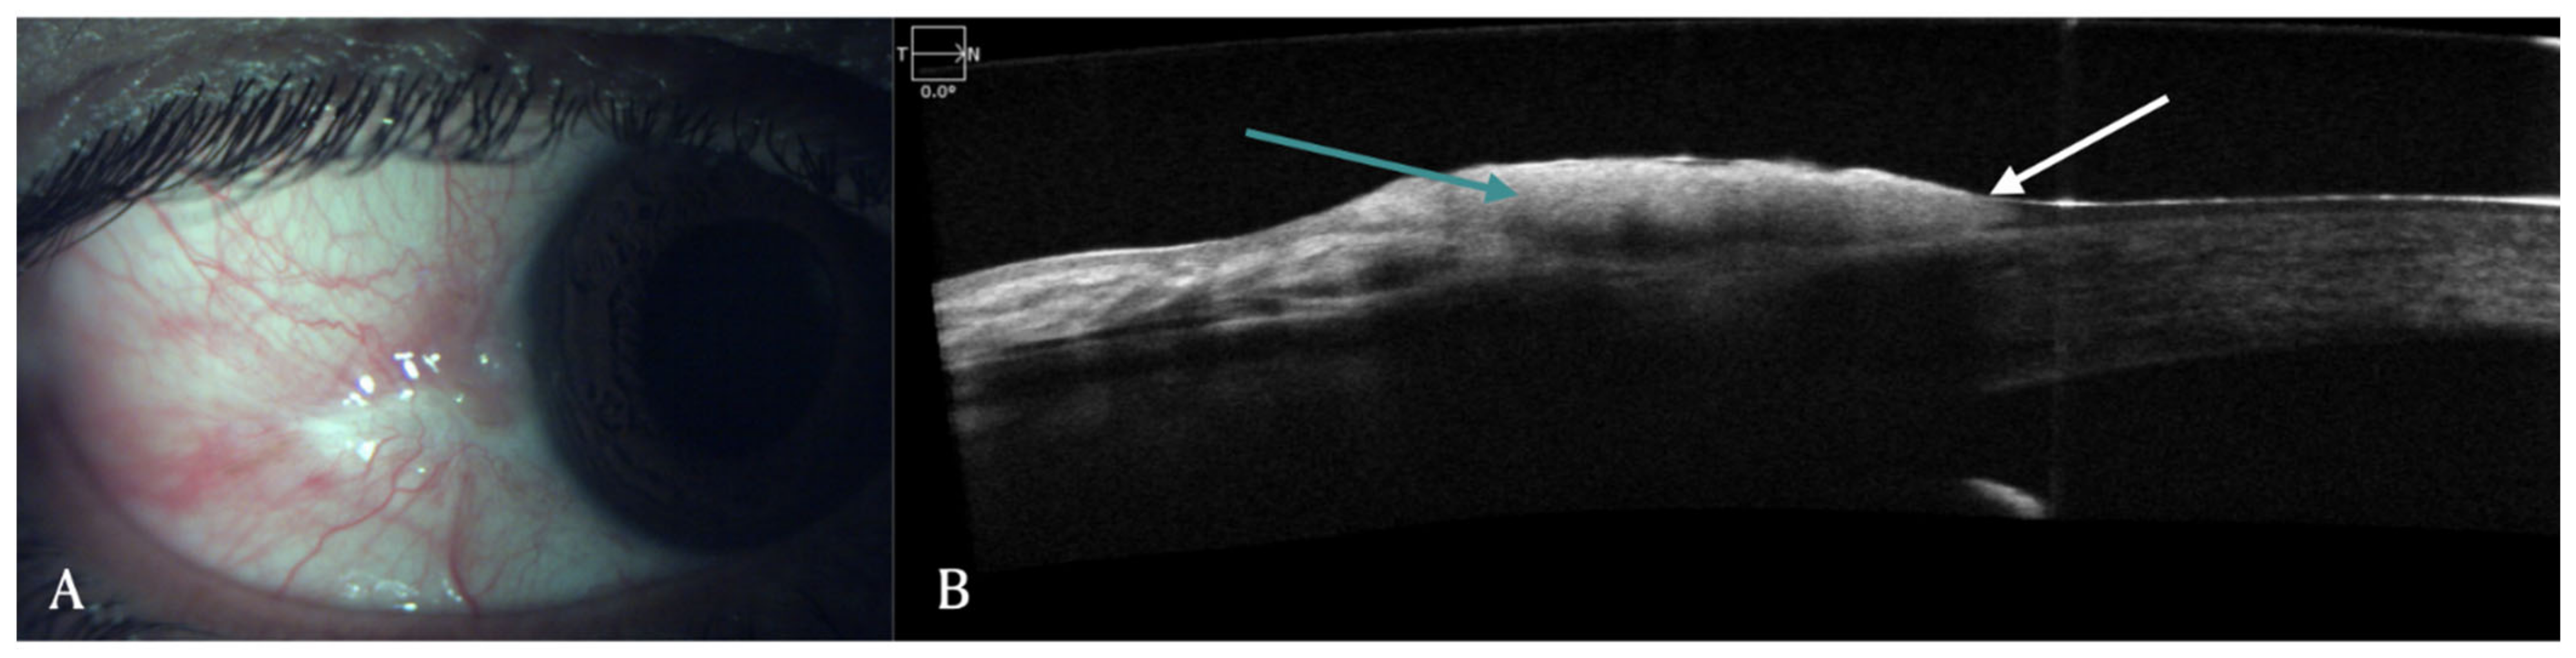

6. Keratoconus